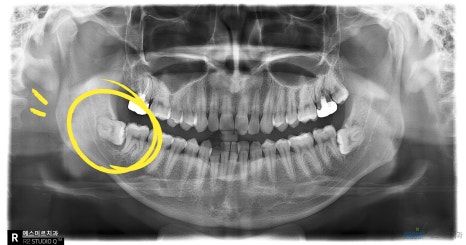

오른쪽 아래 완전매복사랑니 발치 전 후